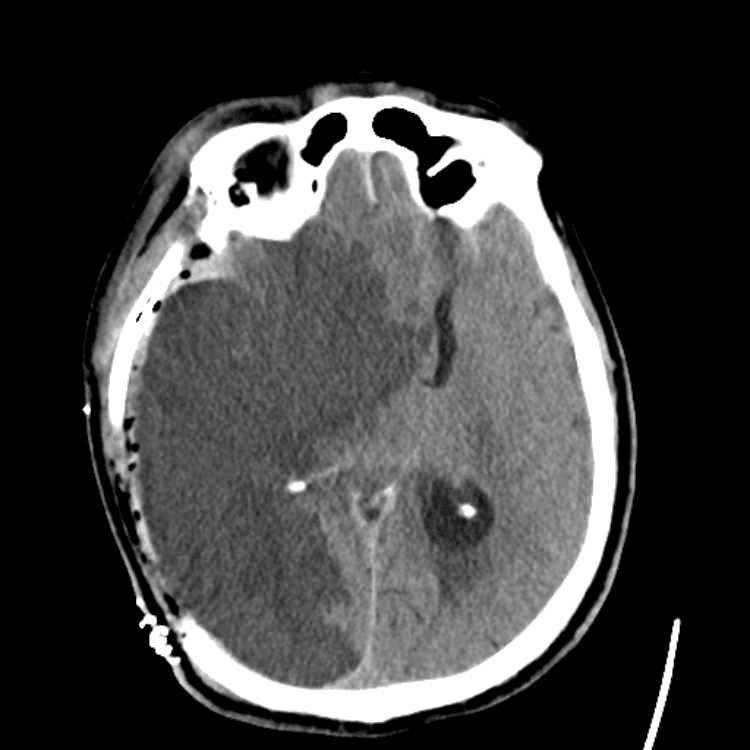

Nontraumatic Brain

Classic